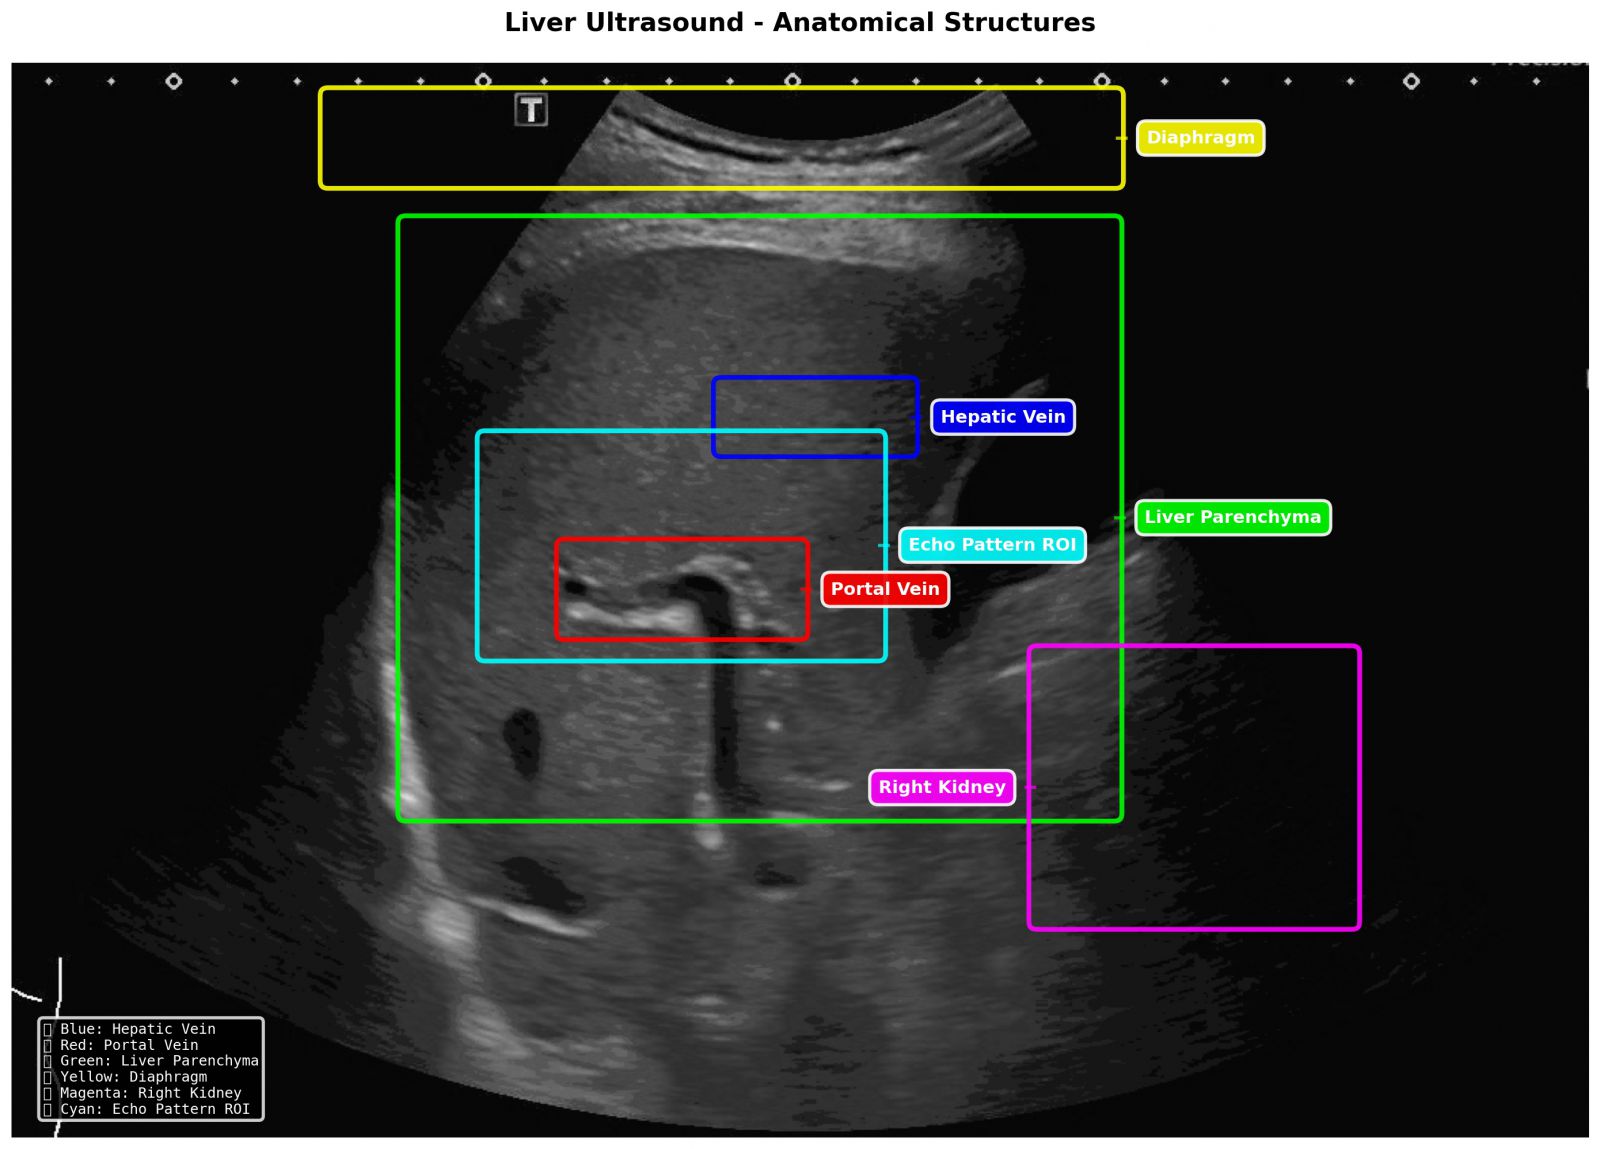

SmartLiva ทำงานเหมือน “อัปเกรด” จากภาพอัลตราซาวด์ขาวดำธรรมดาให้กลายเป็นผลวินิจฉัยที่อ่านง่ายและแม่นยำ โดยแพทย์อัปโหลดภาพผ่านเว็บได้ทั้งบนคอมพิวเตอร์หรือแท็บเล็ต จากนั้นระบบจะช่วยปรับภาพให้ชัดขึ้น คัดเฉพาะบริเวณเนื้อตับที่ต้องวิเคราะห์ และทำให้ภาพดูเข้าใจง่ายขึ้นด้วยการไฮไลต์เป็นสี (เช่น ตับเป็นสีแดง ไขมันเป็นสีเหลือง) เพื่อให้เห็นความผิดปกติได้ทันที โดย AI จะทำการประเมิน 3 เรื่องพร้อมกัน คือ ประเมินระดับพังผืด/ความแข็งของตับ (F0–F4), ตรวจหาความผิดปกติของเนื้อเยื่ออย่างถุงน้ำหรือมะเร็งตับ และตรวจหาพยาธิใบไม้ตับ ซึ่งตัว AI จะทำการประมวล วิเคราะห์ และสรุปผลออกมาเป็นรายงานพร้อมภาพประกอบและคำอธิบายที่คนทั่วไปเข้าใจได้ โดย AI ทั้งหมดถูกฝึกฝน (Train) ด้วยฐานข้อมูลภาพอัลตราซาวด์กว่า 50,000 ภาพ จากโรงพยาบาลชั้นนำ อย่างโรงพยาบาลขอนแก่น โรงพยาบาลจุฬาลงกรณ์ และโรงพยาบาลรามาธิบดี